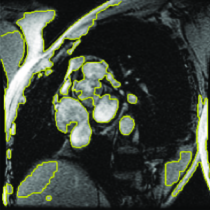

Appearance is one of the most important visual cues to distinguish between different structures in an image. Appearance is described by studying the distribution of different features such as intensity values in gray-scale images, color, and texture inside each object. In most cases, appearance models are incorporated into the data term in (2) and (7). The purpose of incorporating appearance prior is to fit the appearance distribution of the segmented objects to the distribution of objects of interest, e.g. using Gaussian mixture model (GMM) (Rother et al., 2004). In the literature, there are two ways to model the appearance: 1) adaptively learning the appearance during the segmentation procedure, and 2) knowing the appearance model prior to performing segmentation (e.g. by observing the appearance distribution of the training data). In the former case, the appearance model is learned as the segmentation is performed (Vese and Chan, 2002) (computed online). In the second case, it is assumed that the probability of each pixel belonging to particular label is known, i.e. if represents a particular set of feature values (e.g. intensity/color) associated with each image location for object, then it is assumed that is known (or pre-computed offline). This probability is usually learned and estimated from the distribution of features inside small samples of each object. Figure 9 illustrates the probability of different structures (the kidney, the tumour, and the background) in an endoscopic scene. A lower intensity in Figures 9(b-d) corresponds to higher probability.